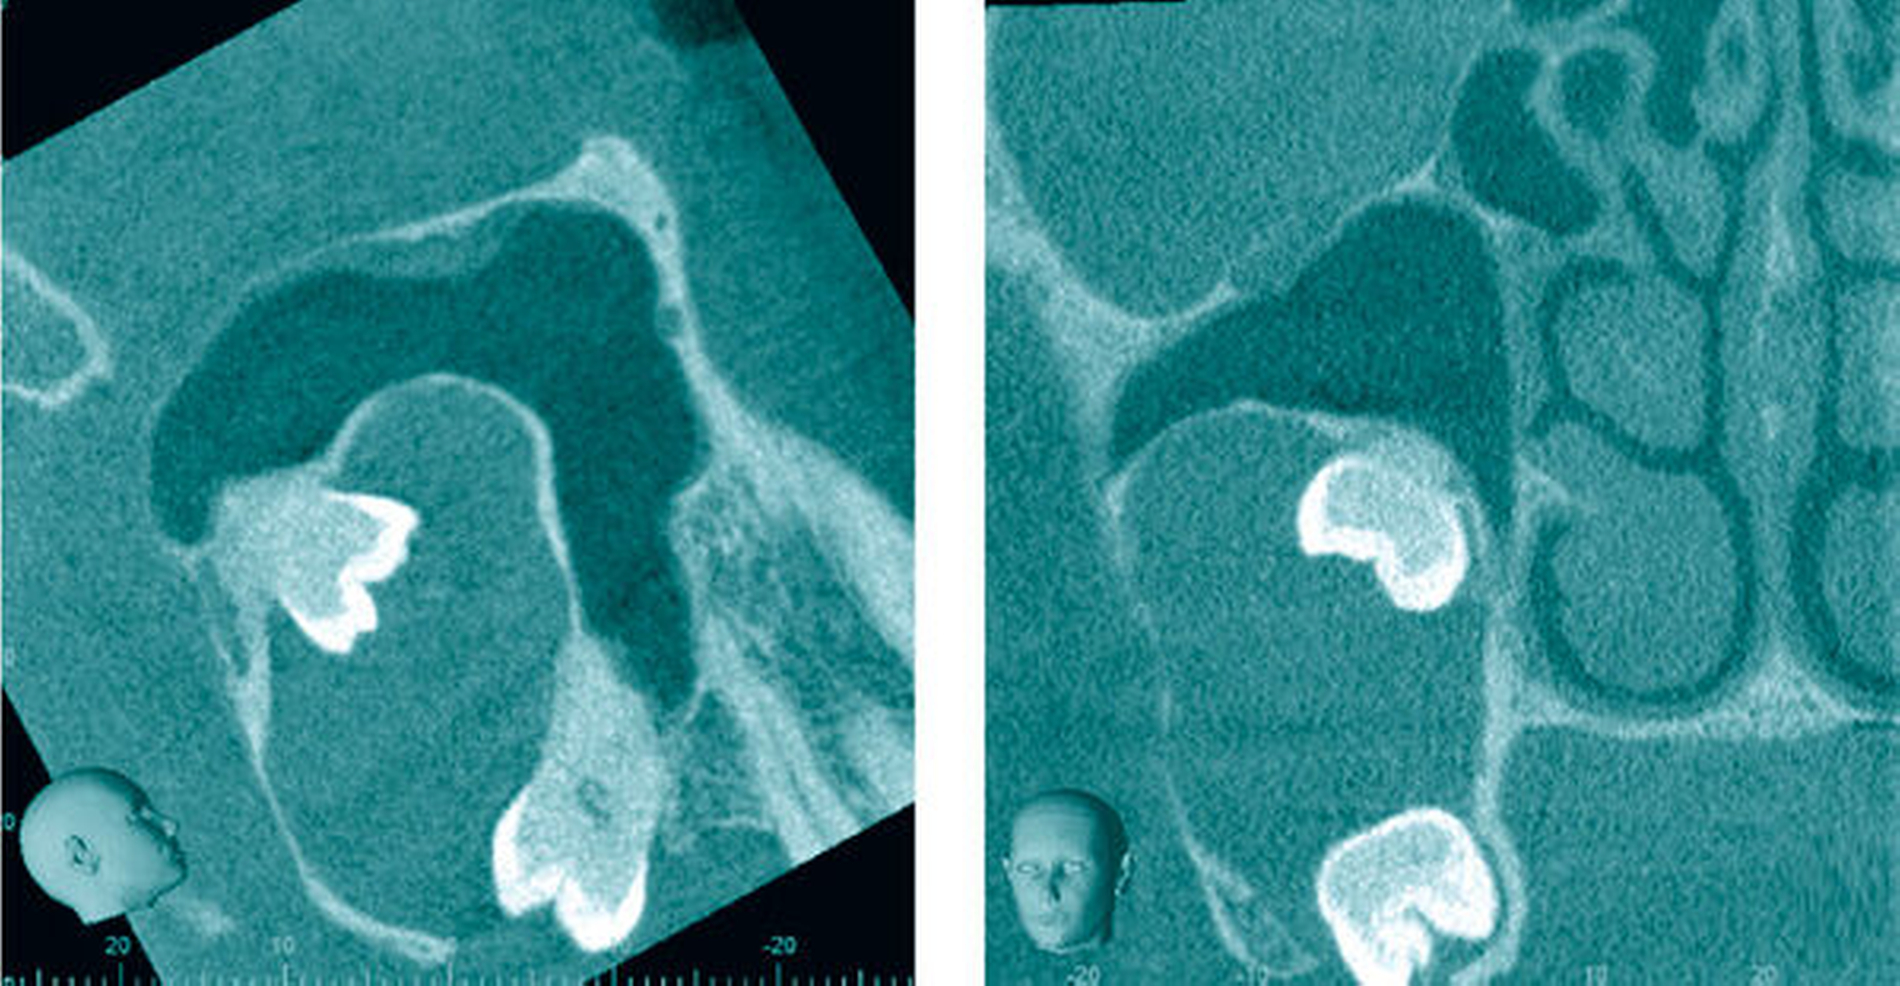

In der Panoramaschichtaufnahme (PAN) projizierten sich der Zahn 17 verlagert am unteren Rand des Sinus maxillaris und der Zahn 18 weiter cranial in der Kieferhöhle. Beide Zähne waren verbunden mit einem ovalen, scharf begrenzten Befund in der Größe einer Walnuss, der von der Krone des Zahnes 18 ausging und distoapikal am Zahn 17 endete (Abbildung 2). Zur Beurteilung wurde eine Dentale Volumentomografie (DVT) angefertigt. In der dreidimensionalen Aufnahme wurde die Ausbreitung der knöchern scharf begrenzten Raumforderung, die bis zum oberen Drittel der Kieferhöhle reichte, sichtbar (Abbildung 3).